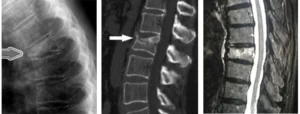

Le fratture vertebrali possono essere traumatiche o patologiche. Le fratture traumatiche derivano da un evento traumatico diretto, come un incidente o una caduta, che provoca la rottura di una vertebra sana. Le fratture patologiche, invece, si verificano quando la vertebra è indebolita da malattie che compromettono la resistenza dell’osso, come l’osteoporosi, i tumori benigni o maligni, l’ipertiroidismo, e i trattamenti chemio- e radio-terapici. Questi fattori rendono le vertebre più suscettibili a fratture anche a seguito di traumi minori, che altrimenti non causerebbero danni in una colonna vertebrale sana.

La frattura vertebrale da compressione è una delle forme più comuni di frattura patologica, che si verifica quando la vertebra perde la sua normale densità ossea e si frantuma sotto il peso o la pressione. In molti casi, le fratture vertebrali da compressione si verificano in pazienti con osteoporosi, una condizione che indebolisce le ossa e le rende più fragili. Inoltre, le fratture vertebrali sono frequentemente associate a tumori che colpiscono la colonna vertebrale, come i tumori maligni primari o le metastasi ossee provenienti da altre parti del corpo.

Le fratture vertebrali, se non trattate correttamente, possono portare a gravi complicazioni come dolore cronico, perdita di mobilità, e in alcuni casi, danni permanenti ai nervi. È quindi fondamentale un intervento tempestivo e mirato per ridurre il dolore e favorire la guarigione. I trattamenti per le fratture vertebrali possono includere radiologia interventistica, tecniche minimamente invasive come la vertebroplastica o la kyphoplastica, che permettono di ripristinare la stabilità della vertebra senza ricorrere a interventi chirurgici tradizionali. Queste tecniche vengono eseguite sotto guida radiologica, garantendo alta precisione e riducendo i rischi per il paziente.